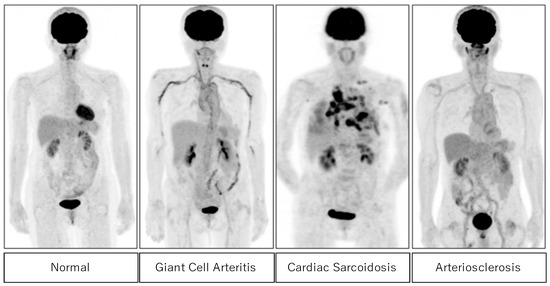

Molecular Imaging for Integrat Tamaki, Nagara; Kuge, Yuji 18F-Fluorodeoxyglucose Imaging for Assessing Cardiovascularの詳細情報

18F-Fluorodeoxyglucose Imaging for Assessing Cardiovascular。Imaging of C-X-C Motif Chemokine Receptor 4 Expression in。Synthesis, preclinical, and initial clinical evaluation of。

MolecularImagingforIntegrat

TamakiNagara

2009/11/01

4431980733

9784431980735

MolecularImagingforIntegrat

TamakiNagara

2009/11/01

4431980733

9784431980735